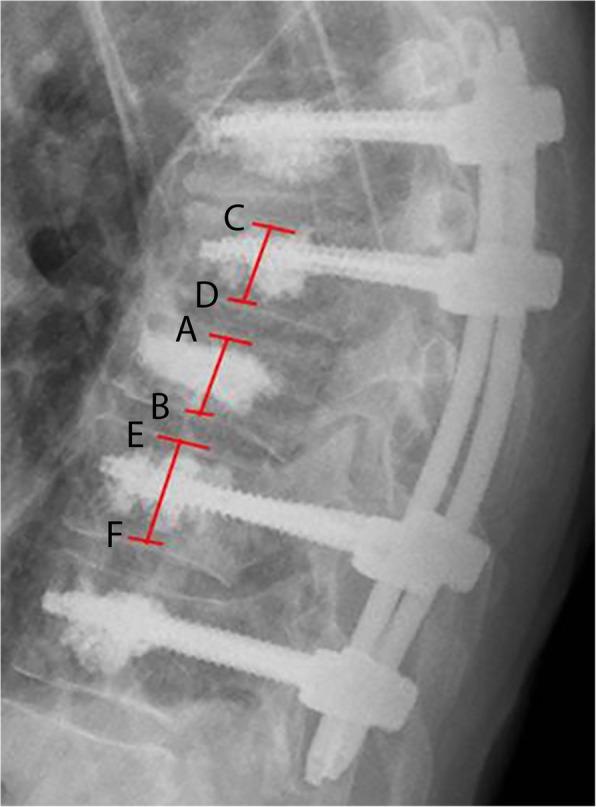

Retrospectively, all patients aged ≥65 suffering from an acute unstable midthoracic fracture treated with posterior stabilization were included. Trauma mechanism, ASA score, concomitant injuries, ODI score and radiographic loss of reduction were evaluated. Posterior stabilization strategy was divided into short-segmental stabilization and long-segmental stabilization.

Fifty-nine patients (76.9 ± 6.3 years; 51% female) were included. The fracture was caused by a low-energy trauma mechanism in 22 patients (35.6%). Twenty-one patients died during the follow-up period (35.6%). Remaining patients (n = 38) were followed up after a mean of 60 months. Patients who died were significantly older (p = 0.01) and had significantly higher ASA scores (p = 0.02). Adjacent thoracic cage fractures had no effect on mortality or outcome scores. A total of 12 sequential vertebral fractures occurred (35.3%). The mean ODI at the latest follow up was 31.3 ± 24.7, the mean regional sagittal loss of reduction was 5.1° (± 4.0). Patients treated with long segmental stabilization had a significantly lower rate of sequential vertebral fractures during follow-up (p = 0.03).